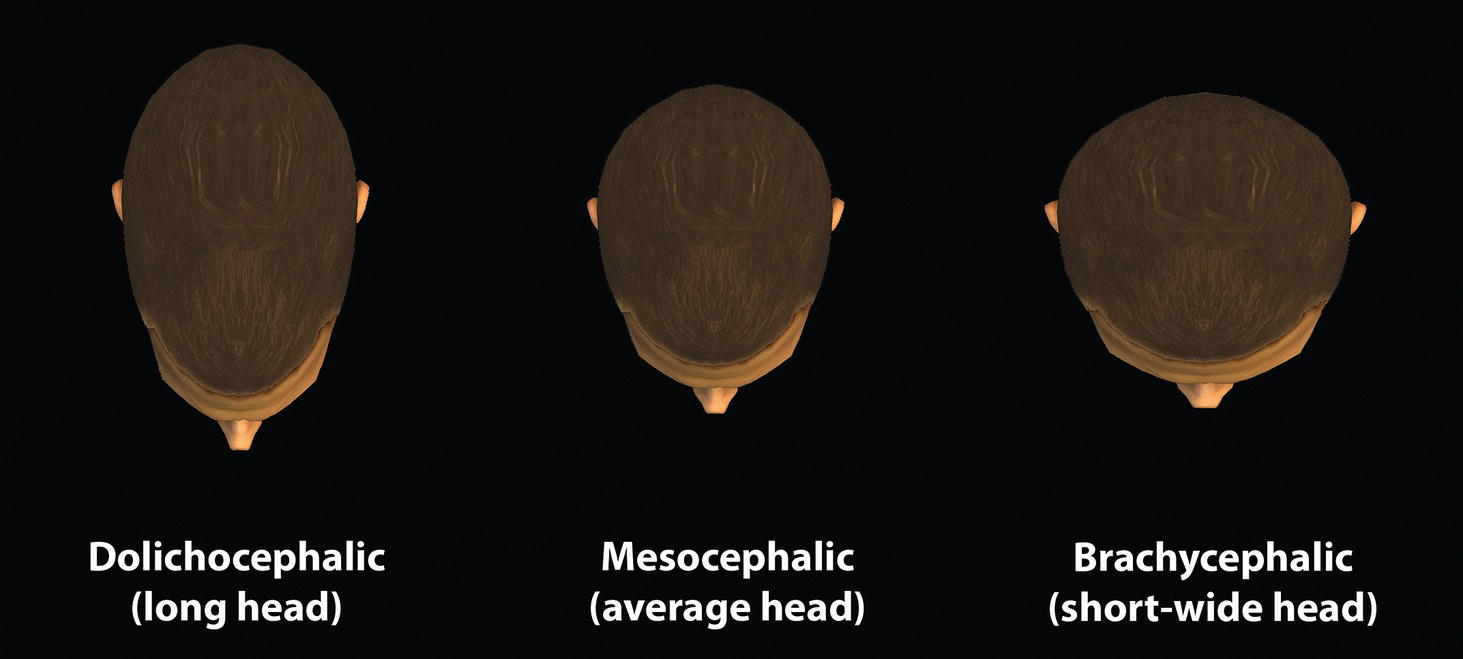

‘It is the common wonder of all men, how among so many millions of faces, there should be none alike’. Sir Thomas Browne (1605–82), English physician and writer, Religio Medici (1643)1 Individual variability is a fundamental principle in human biology. One of the most variable and distinguishable parts of the human body is the craniofacial complex. Clinicians will often compare a patient’s craniofacial measurements and proportions to the so‐called population norms (normative values) or even to classical ideals. However, Simon (1926) stated: ‘all we ever find are variations; an exact, ideal normal does not exist, cannot exist. And this is our enigma; in theory we will never find the normal, in practice we forever feel its need and apply it constantly’.2 The use of population norms may be logically enhanced by evaluating normal ranges of variability. Therefore, clinicians must have a thorough understanding of the normal ranges of variability in every aspect of craniofacial form, depending on age, sex and ethnic variability. Developmental disorders, as well as traumatic injuries and pathological conditions, may lead to deformities of the head and the face. Therefore, clinicians need to have a thorough understanding of the normal anatomy and morphological range of variation of the craniofacial complex in both males and females of different ages and ethnic groups, to act as guidelines when treatment planning the restoration of normal craniofacial proportions. Classifications that are useful for descriptive purposes include: A proportion index provides a numerical expression of the proportionality of a region of the craniofacial complex. The use of proportion indices dates back through the history of craniometry, particularly in the late nineteenth century. Linear (chord) or surface (arc) distances of the skull were measured between a variety of defined craniofacial landmarks; with any two measurements, the smaller was expressed as a percentage of the larger in order to provide a proportion index value. These could be used to provide an indication of skull shape. Figure 8.1 Determination of the normality or abnormality of any craniofacial measurement (or proportion index value) obtained from patients may be evaluated by comparison with the normative values obtained from a normal (average representative) population sample. The normal range of measurements is provided by the mean ±2 standard deviations (SD). The shape of the normal distribution curve shown is determined by the population standard deviation. Craniofacial parameters with small SDs have narrow, taller curves and those with large SDs have broader, flatter curves. Approximately 68% of all values fall within the range of ±1 SD from the mean and 95% within the range of ±2 SD from the mean. The normal range of variability for any craniofacial parameter is taken as being equal to the mean ±2 SDs. Greater differences may be perceived as deformities of gradually increasing severity. The leading researcher in the field of craniofacial anthropometry from the mid‐1960s to the early 2000s was Leslie Farkas, from the University of Toronto. Farkas et al. collected a large quantity of highly relevant anthropometric data between 1968 and 1984, from 2564 individuals.3 These data were used to provide 166 individual facial ratios, presented as proportion indices. In the creation of an index, the smaller measurement is multiplied by 100 (numerator) and divided by the larger measurement (denominator). Thus, a proportion index involves two linear craniofacial anthropometric measurements, with the smaller being expressed as a percentage of the larger. Proportion indices permit objective, quantitative assessment of facial morphology and proportions. Farkas3 identified two basic categories of proportion indices: Each proportion index will have a mean index value and a range of variation for a given population group, based on age, sex and ethnicity. The standard deviation (SD) determines the normal (average) range of variability of an index, from 2 SD below to 2 SD above the mean. Index values within this normal range are regarded as variations of normal proportions.4 Measurements within ±1 SD of the mean are regarded as optimal. The relationship between two measurements is disproportionate if the proportion index value is outside the normal range (Figure 8.1).4 For a number of facial parameters, single morphological measurements or proportion index values may have a large SD and, therefore, wide normal ranges of variation; as such, only measurements or proportion index values which differ considerably from the mean of the population will be perceived as deformities. Conversely, other facial parameters may have very small normal ranges of variability, in which case even a small difference from the mean may be perceived as a deformity. The cephalic index (index cephalicus) is a numerical expression of the ratio between the head width (biparietal diameter) and head length (fronto‐occipital diameter) of a living person. The cephalic index (CI) is calculated by the formula (Figure 8.2): Figure 8.2 Cephalic index. Where: The cephalic index is used in anthropometry to classify head types as (Table 8.1; Figure 8.3): Table 8.1 Classification of anatomical head types Index values according to Martin and Saller.5 Figure 8.3 Head types. The highest cephalic index values occur in the Chinese and the lowest values in African Americans. The larger index values of the Chinese differ significantly from those of whites or blacks (Table 8.2).6 A comparison of the cephalic index values of three ethnic groups was undertaken; North American Caucasians, northern European (German) and eastern European (Czech). The index values indicated a mesocephalic head type for both sexes of North American Caucasians and northern Europeans; and a brachycephalic (short‐wide) head type for the eastern Europeans.6 The head circumference is measured in the horizontal plane around the head, through the glabella and opisthocranion. However, it may be measured across ophyron (the point ‘On’, in the mid‐sagittal plane, of a line tangent to the upper limits of the eyebrows) rather than glabella in order to eliminate the effect of development of the frontal sinuses and superior orbital rims on head circumference.5,7 African Americans have the largest and the Chinese have the smallest head circumference for both sexes. The head circumference is slightly larger for blacks than for whites for both sexes.6 The initial step in facial analysis involves the examination of the face in frontal view in order to assess the overall facial shape. The variety of facial shapes is almost limitless. However, a simple assessment will allow an overall categorization of the basic facial shape. The basic facial shape in frontal view may be any combination of the following: Table 8.2 Cephalic index of three ethnic groups Data modified from Farkas.6 SD = standard deviation. Table 8.3 Head circumference of three ethnic groups Data modified from Farkas.6 SD, standard deviation. Figure 8.4 Facial height‐to‐width ratios. Variations in facial height and width result in an innumerable variety of the three basic facial shapes (round, square and triangular). For example, an oval facial type is a combination of an overall round face combined with increased vertical facial height and/or reduced facial width. The relationship of vertical facial height to facial width is an important indicator of overall facial shape. There are three methods of evaluating the vertical facial height‐to‐width proportion. These may be presented as proportions, percentages or indices: The facial index (index facialis or index of the morphological face height) is a numerical expression of the ratio between the facial height (nasion to menton) and the bizygomatic facial width (zygion to zygion) of a living person. The facial index (FI) is calculated by the formula: Where: The facial index is used in anthropometry to classify faces as (Table 8.4; Figure 8.6): Figure 8.5 Facial types according to Albrecht Dürer. (Modified from Dürer, 15288.) Figure 8.6 Facial types. Table 8.4 Classification of anatomical face types Index values: male according to Garson, 1885;9 and female according to Martin and Saller, 1957.5 The term facial divergence was introduced by the orthodontist‐anthropologist Milo Hellman,10 although the concept had been described by Albrecht Dürer (1528) (Figure 8.7).8 It is essentially a description of the slope or inclination of the face in the sagittal plane (Figure 8.8). It is determined by the sagittal position of soft tissue pogonion (Pog’) and subnasale (Sn) relative to a vertical line dropped from glabella (G’), with the subject’s head in natural head position. The factor that discriminates and distinguishes facial divergence from profile convexity or concavity is the sagittal position of subnasale (Sn) relative to the G’‐Pog’ line. In order for the face to diverge anteriorly or posteriorly, yet not to exhibit signs of convexity or concavity, subnasale (Sn) must be on or nearly on the G’‐Pog’ line; i.e. the upper facial plane (UFP, G′‐Sn) and the lower facial plane (LFP, Sn‐Pog’) are in a straight line, but diverge anteriorly or posteriorly. Figure 8.7 Facial divergence according to Albrecht Dürer. (Modified from Dürer, 15288.) Figure 8.8 Facial divergence. Anthropometric data from North American Caucasian males and females with untreated Class I dental occlusions describing normal facial divergence and ranges of variability has been provided.11 Mean values of facial divergence are negative, with the faces being slightly posteriorly divergent. Anterior divergence does not occur until two standard deviations from the mean. Facial divergence is essentially an ethnic variation in facial profile form. With a straight profile, i.e. no excessive profile convexity or concavity, anterior or posterior facial divergence is compatible with a normal maxillo‐mandibular and dental occlusal relationship. Figure 8.9 Facial profile contour according to Albrecht Dürer. (Modified from Dürer, 15288.) Figure 8.10 Facial profile contours. The contour of the facial profile may be described as convex, straight or concave. This concept was described by Albrecht Dürer (1528) (Figure 8.9).8 With the patient in NHP, the overall contour of the facial profile may be described by the relationship between two lines: the upper facial plane (UFP), connecting glabella (G’) to subnasale (Sn), and the lower facial plane (LFP), connecting subnasale to soft tissue pogonion (Pog’). In a straight profile, these two lines form a nearly straight line. Such a facial profile is termed orthognathic (Greek orthos: correct or straight; gnathos: jaw). An angle between these two lines indicates facial profile convexity (pogonion behind relative to subnasale in the sagittal plane), or facial profile concavity (pogonion ahead relative to subnasale in the sagittal plane). A convex profile indicates a skeletal Class II jaw relationship (and/or sagittal chin deficiency), and a concave profile indicates a skeletal Class III jaw relationship (and/or sagittal chin excess). However, profile convexity or concavity does not of itself indicate whether the maxilla or mandible/chin is at fault (Figure 8.10). Legan and Burstone12 described the angle of facial convexity for the soft tissue profile. It is formed by the two intersecting lines, the UFP (G′‐Sn) and the LFP (Sn‐Pog′). The mean value is estimated to be 12° ± 4°. An increase in the angle in a clockwise direction is positive; anticlockwise is negative. A high positive value suggests facial profile convexity and a Class II skeletal jaw relationship; a smaller positive value, or a negative value, suggests facial profile concavity and a Class III skeletal jaw relationship. However, the value of this angle does not reveal whether the maxilla or mandible/chin is responsible for the sagittal jaw discrepancy. Figure 8.11 Angle of facial profile convexity (facial contour angle). Downs13 described the angle of convexity, formed by the intersection of line nasion to point A (NA) and line point A to pogonion (A‐Pog). Superior extension of the A‐Pog line forms an angle with the NA line; if behind the NA line, the angle is read as positive, indicating a Class II (convex) skeletal profile. A negative angle of convexity indicates a Class III (concave) skeletal profile. Downs provided a range of values from −8.5° to 10°, with a mean of 0°. Again, as with the facial contour angle, the angle of convexity does not determine the localization of the deformity to the maxilla or mandible/chin. An investigation was carried out with the objective of assessing how lower facial profile convexity influences perceived attractiveness. The lower facial profile of an idealized image was altered incrementally between 14° and −16°, creating a range of images which were evaluated by pretreatment orthognathic surgery patients, laypeople and clinicians. A straight profile was perceived as most attractive and greater degrees of convexity or concavity deemed progressively less attractive, but a range of 10° to −12° was deemed acceptable; beyond these values surgical correction was desired. Patients were most critical, and clinicians were more critical than laypeople.14 The facial angle indicates the relative sagittal prominence of soft tissue pogonion. It is formed by the intersection of the true horizontal plane (or Frankfort Horizontal plane) with a facial vertical plane (N′‐Pog’). The angle should be approximately 90°–92°. A greater angle indicates prominence of soft tissue pogonion; an angle less than 90° indicates retrusion of soft tissue pogonion. The soft tissue facial angle does not of itself determine the aetiology of the sagittal position of soft tissue pogonion, which may be due to one or a combination of: Consequently, the facial angle must be used in conjunction with other measurements and analyses. In addition, when constructing the facial vertical line (N’‐Pog’), if the sagittal position of nasion is not acceptable, it may be adjusted to a more ideal position. The alternative is to use soft tissue glabella (G’) rather than nasion. Downs13 described the facial angle as the inferior inside angle in which the facial line (N‐Pog) intersects the Frankfort Horizontal plane. Downs found a mean value of 88° with a range of 82°–95°. It indicates the relative sagittal position of the mandible/chin to the upper face. Figure 8.12 Facial angle. FH, Frankfort Horizontal plane; TrH, true horizontal plane. Figure 8.13 The relationship of the cranial base angle (saddle angle) and anterior cranial base length on the jaw relationship. The relationship of the anterior to the posterior cranial base is of particular importance in the diagnosis of facial profile contour. This relationship depends on the extent of growth at the sphenoethmoidal and spheno‐occipital synchondroses. The cranial base angle (or saddle angle) represents the orientation of the anterior cranial base (SN line) relative to the posterior cranial base (S‐Ba line).15 The average adult values (bearing in mind that there is negligible change in this angle after the age of six years) for the angle N‐S‐Ba are16: As such, the cranial base angle is an important determinant of craniofacial form, as it influences the sagittal position of the face relative to the neurocranium and the sagittal prominence of the mandible relative to the maxilla. A significantly increased cranial base angle contributes to a skeletal Class II jaw relationship, whereas a reduced cranial base angle contributes to a skeletal Class III jaw relationship. If basion is difficult to identify on a lateral cephalometric radiograph, articulare may be used instead, i.e. the posterior cranial base is drawn between sella and articulare. The average adult values for the angle N‐S‐Ar are16: The anterior cranial base length, measured from sella to nasion, may also influence the jaw relationship. For example, increased anterior cranial base length may lead to a Class II jaw relationship, with the maxilla ahead of the mandible in the sagittal plane, whereas reduced cranial base length may lead to a Class III jaw relationship, with the maxilla behind the mandible in the sagittal plane. The average adult values for the anterior cranial base length are16: Figure 8.14 Parasagittal profile contour. An additional and extremely important consideration is the description of the parasagittal profile (Figure 8.14). It is necessary to evaluate the sagittal relationships of the soft tissues from the infraorbital area to the paranasal area to the parasymphyseal area. For example, maxillary hypoplasia may lead to lack of bony support and flattening in the infraorbital region and paranasal hollowing; with a normal parasymphyseal area, this will lead to the appearance of a concave parasagittal profile. The directional pattern of facial growth has a significant effect on facial profile form. Deviations from the normal pattern of jaw growth may be in a predominantly vertical or horizontal direction. Alternative terms are hyperdivergent facial growth pattern (referring to the excessive divergence of the maxillary, occlusal and mandibular planes in relation to each other and to the anterior cranial base).17 Such a pattern of growth leads to a hyperdivergent facial type, alternatively termed a high angle patient (referring to the increased mandibular plane angle), long face deformity or long face syndrome.18 If the hyperdivergent growth is the primary aetiology to an anterior open bite, the terms skeletal open bite or apertognathia (Latin apertus: open; Greek gnathos: jaw) may be used.19,20 The maxilla rotates downward and backward (posterior vertical maxillary excess), as does the mandible during growth. This leads to reduced sagittal projection of the chin. Such a vertical facial growth pattern will tend to be associated with a posterior pattern of mandibular growth rotation. Figure 8.15 Hyperdivergent, ‘high angle’ facial type.